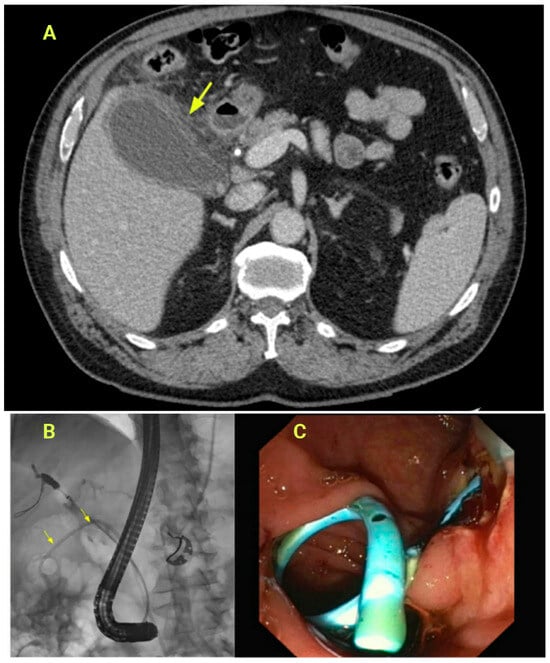

3.13. Pancreatic Fluid Collection and Duct Leak